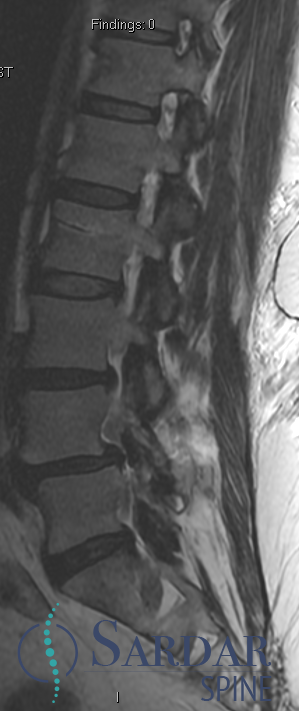

From robotics and AI-driven surgical planning to virtual modeling and custom implants, I’ve embraced a combination of tools that allow me to create tailored surgical plans for my patients—particularly those with scoliosis and spinal deformities.

What sets my approach apart is the seamless integration of these advanced technologies to ensure unparalleled accuracy and better outcomes for each patient.